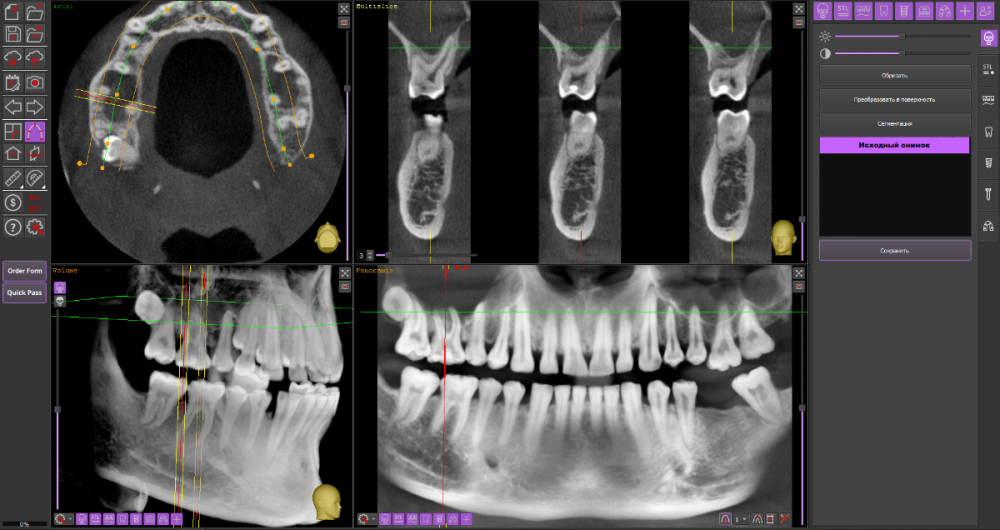

Mnrg Опубликовано 6 июля, 2023 Поделиться Опубликовано 6 июля, 2023 Всех приветствую! Беспокоит правосторонний гайморит и тонзиллит. Сделали КТ, нашли восьмерку, но предложили вместо удаления восьмерки депульпировать шестерку, консилиум сошелся во мнении, что корень перфорирует пазуху и пломба слишком близко к нерву, возможно воспаление. При зондировании между 6 и7 слегка побаливает десна, шестерка не беспокоит, холод чувствует, но не болит. Восьмерку предложили оставить. Спорить не стал, лишь решил собрать воедино мнения специалистов, т.к ближайшие более менее нормальные клиники от 100км. Архив с файлами КТ прикрепил, прошу специалистов глянуть и поделиться мнением, с чего все-таки начать, помочь разобраться.Archive.rar Ссылка на комментарий

wladdX Опубликовано 7 июля, 2023 Поделиться Опубликовано 7 июля, 2023 (изменено) Гайморит у вас совершенно необязательно имеет одонтогенную природу (вызван зубами). Судя по КТ, зуб 16 может быть виновником (а может и не быть). Для уточнения нужна также проверка витальности его пульпы (жив нерв или нет). Если пульпа нежизнеспособна, то этот зуб почти наверняка поддерживает воспалительный процесс в пазухе. Зуб 18 вряд ли нужно трогать. Лежит он себе в кости и пускай, никому он там не вредит. Да он вплотную прилежит к корням зуба 17, но и только. С внешней средой не контактирует. Никакого негативного влияния на соседние зубы он оказывать не должен: формирование корней завершено, потенции к росту и какому-либо движению нет. Удаление зуба 18 в данной ситуации вряд ли оправдано. Процедура не самая простая, но и не запредельной сложности. Изменено 7 июля, 2023 пользователем wladdX Ссылка на комментарий

Mnrg Опубликовано 7 июля, 2023 Автор Поделиться Опубликовано 7 июля, 2023 6 минут назад, wladdX сказал: Гайморит у вас совершенно необязательно имеет одонтогенную природу (вызван зубами). Судя по КТ, зуб 16 может быть виновником (а может и не быть). Для уточнения нужна также проверка витальности его пульпы (жив нерв или нет). Если пульпа нежизнеспособна, то этот зуб почти наверняка поддерживает воспалительный процесс в пазухе. Зуб 18 вряд ли нужно трогать. Лежит он себе в кости и пускай, никому он там не вредит. Да он вплотную прилежит к корням зуба 17, но и только. С внешней средой не контактирует. Никакого негативного влияния на соседние зубы он оказывать не должен: формирование корней завершено, потенции к росту и какому-либо движению нет. Удаление зуба 18 в данной ситуации вряд ли оправдано. Процедура не самая простая, но и не запредельной сложности. Шестерку проверяли холодом - чувствует, не знаю, означает ли это жизнеспособность пульпы, но на холод реагировал немного сильней других зубов. Сегодня открыл КТ программой RadiAntViewer и обнаружил в 3D просмотре визуальные признаки нахождения части восьмерки в краю пазухи. Конечно я не могу утверждать, т.к не врач и насколько понимаю это режим моделирования, но все же выглядит убедительно на мой скромный взгляд. Еще один глупый вопрос, если позволите) Возможно ли в шестерке в одном из трех корней воспаление и нерв разрушен, а другие два при этом будут создавать чувствительность, т.е быть "живыми" или же это фантастика? Деньги запросили немалые для нашего региона за депульпацию (13к) поэтому пытаюсь собрать как можно больше информации прежде, чем принимать решения. Ссылка на комментарий

wladdX Опубликовано 8 июля, 2023 Поделиться Опубликовано 8 июля, 2023 Ничего нового добавить к своим словам я не могу. Разве что повторить : "Гайморит у вас совершенно необязательно имеет одонтогенную природу". Т.е. надо рассматривать возможность ЛОР-патологии в чистом виде. Если зуб 16 с живой пульпой, то других одонтогенных причин при помощи данного КТ исследования я не вижу. На истину в последней инстанции не претендую. 1 1 Ссылка на комментарий